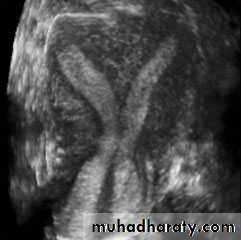

• Intramural leiomyomata are frequently visualized. Examples of fibroids which compromise the contours of the endometrial cavity are shown (A–D). Refraction artifacts resulting from tissue density interfaces and the texture of the fibroids often aid in their identification.Congenital anomalies of uterus

Unicornuate uterusCongenital anomalies of uterus